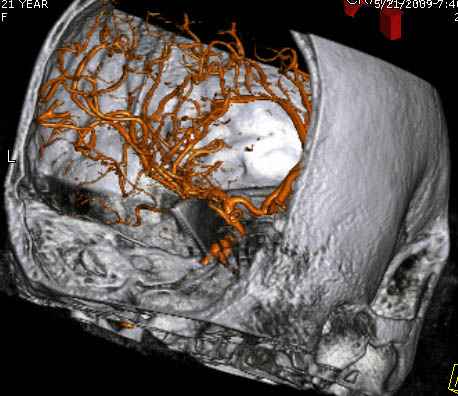

По протоколу сделаны все необходимые исследования: рентген, ангиограмма с 3Д реконструкцией, где обнаружили что все жизненно важные сосуды не задеты, даже некоторые "сидят" изгибаясь на ноже.